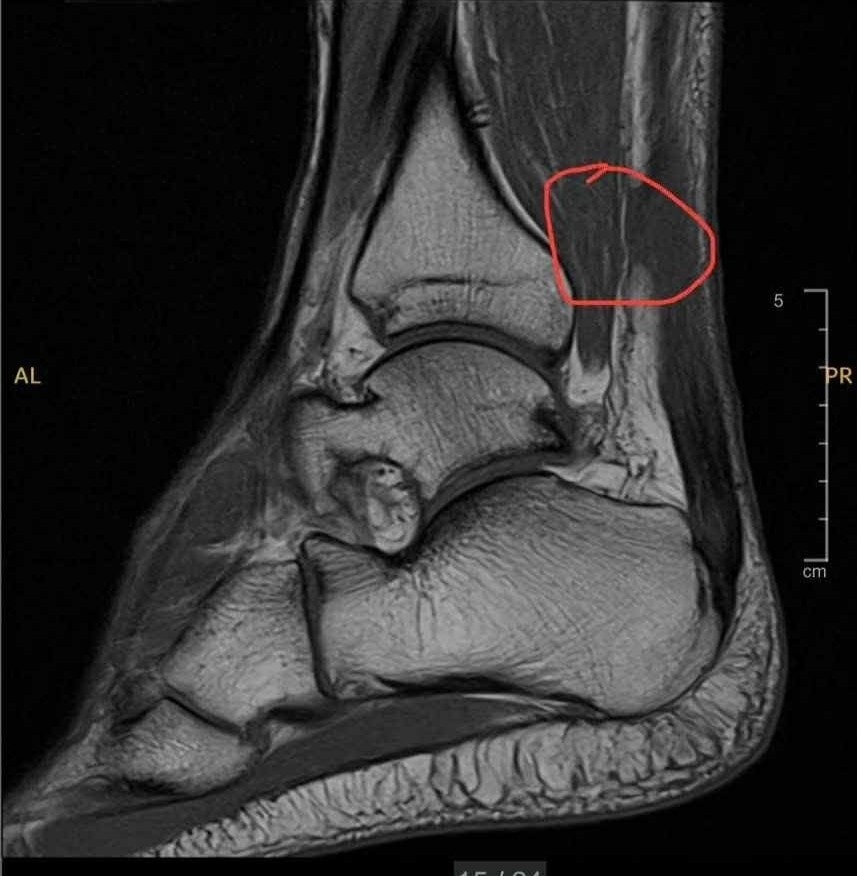

Chia sẻ với Tri Thức - Znews, diễn viên Lật mặt 7 tiết lộ mới bị chấn thương khi chơi pickleball. Ban đầu, anh còn chủ quan nhưng sau đó đã đi chụp MRI vì tình trạng ngày càng nặng. Bác sĩ cho biết anh bị đứt gân chân, phải trải qua phẫu thuật. "Ngày mai bác sĩ hẹn tôi tới khám lại. Còn lịch phẫu thuật để nối lại gân chân dự kiến là trong tuần sau", diễn viên sinh năm 1978 cho hay.

Trương Minh Cường cho biết phải phẫu thuật để nối gân chân vào tuần sau.